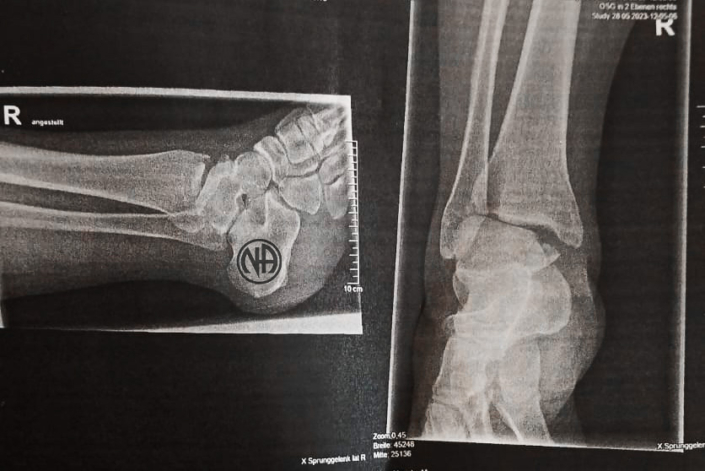

Doch am letzten Tag der Veranstaltung veränderte sich alles. Bei meinem Checkout aus der Ferienwohnung, in der ich während der Convention gewohnt hatte, rutschte ich auf der Treppe aus und brach mir den Fuß.